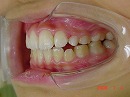

前歯の歯並びが乱れている子供の症例。<出っ歯> 医療法人社団 クオリタス いずみ歯科矯正歯科医院 (浦安市)

前歯の歯並びが気になり来院される患者さんが多いです。

今回の症例は独自の方法とt4kなどによって改善しました。

治療開始時 治療終了時